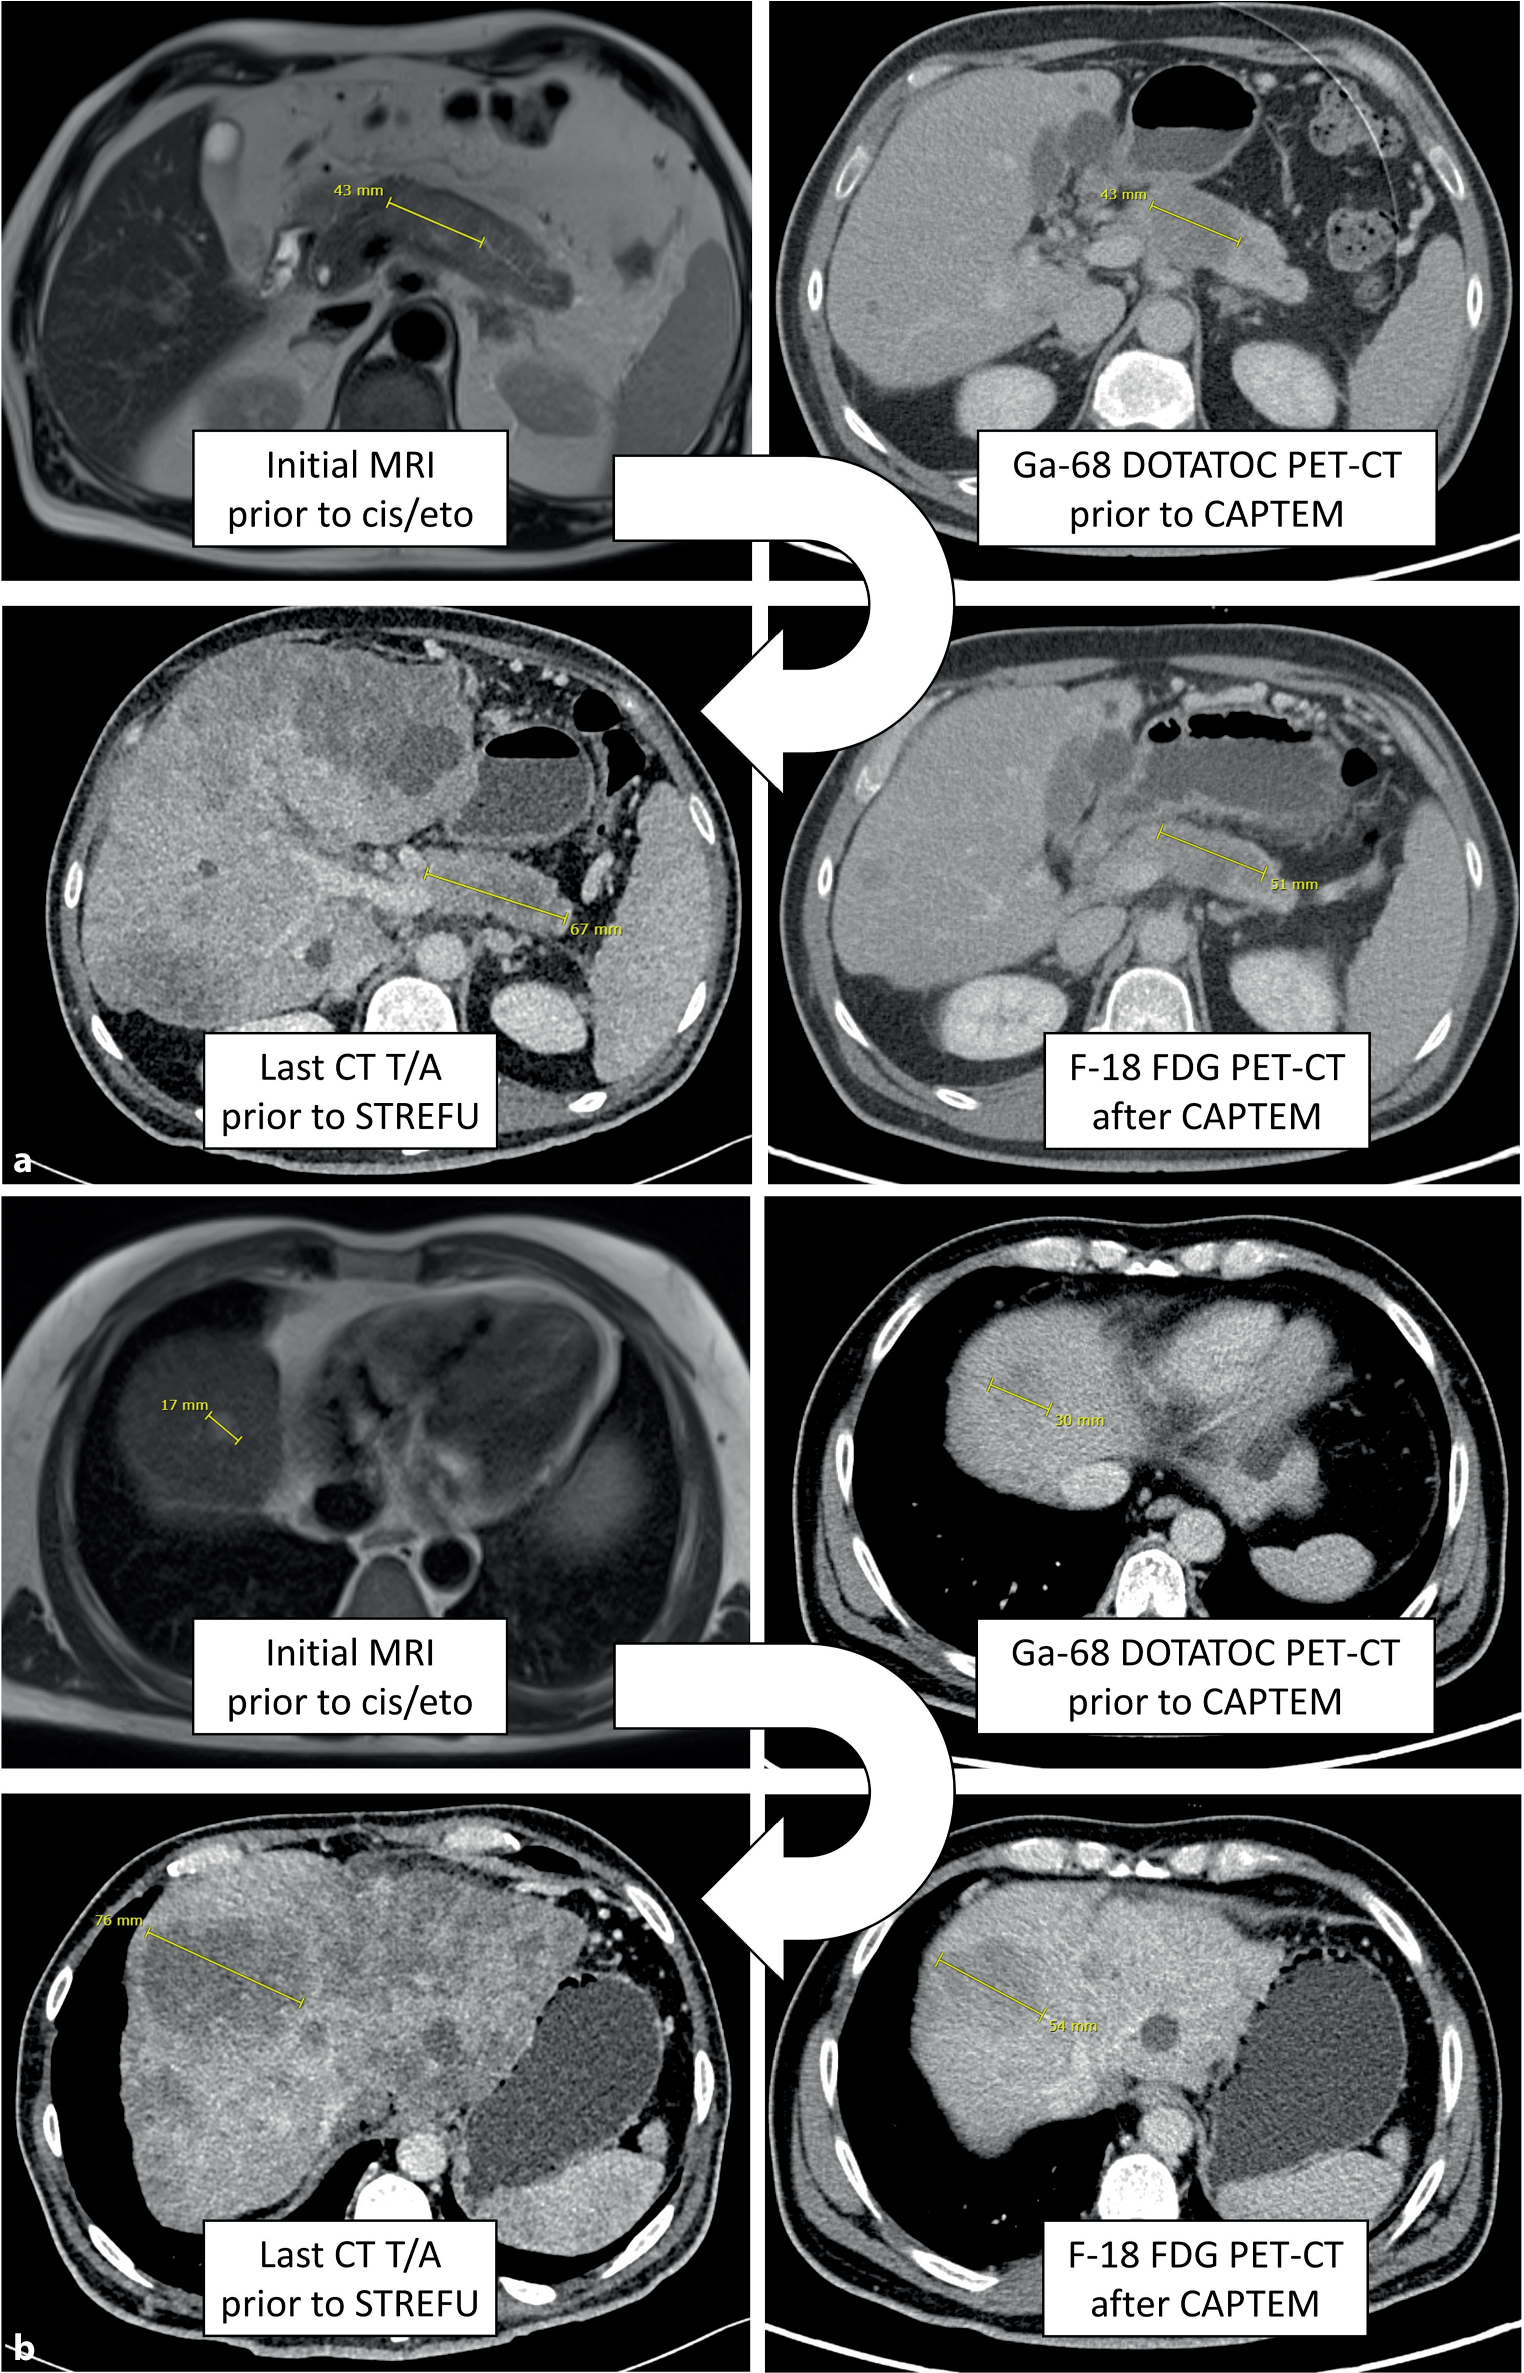

A 49-year-old man was referred to our clinic in mid-2021 for treatment of a pancreatic NEN G3. One month earlier, following recurrent upper abdominal discomfort and an ultrasound-detected lesion in the pancreas, a thoracic/abdominal computed tomography (CT) scan revealed a 3.6 cm mass in the body of the pancreas suspicious for malignancy, and a consecutive magnetic resonance imaging (MRI) visualized multiple hepatic lesions, measuring up to 1 cm in size. Via endoscopic ultrasound-guided fine needle biopsy (EUS-FNB) of the pancreas, a diagnosis of a pancreatic NET of grade 3 (Ki-67 up to 50%) was established. The patient had no significant medical history and was in excellent general condition (Eastern Cooperative Oncology Group [ECOG] performance status 0, no allergies or daily medication). Surgery was not indicated by multidisciplinary tumor board (MDTB) decision and due to the relatively high proliferation rate, the patient was started on cisplatin/etoposide (25 mg/m2 and 100 mg/m2, respectively, d1–3, q21) for 3 cycles (Fig. 1). The restaging CT scan after three cycles confirmed suspected disease progression with new liver lesions and a primary tumor that was minimally progressive in size (Fig. 2). A Ga-68 DOTANOC positron emission tomography (PET)-CT was performed (more likely to be positive in NET G3 than in NEC), but no relevant somatostatin receptor (SSTR)-expressing lesions were detected, with only scattered positivity in the liver. Thus, second-line chemotherapy with capecitabine/temozolomide (CAPTEM, 2500 mg daily in two doses for d1–14 and 250 mg d1–5 every 4 weeks) was recommended by our MDTB. After 3 cycles, a CT scan confirmed disease stabilization. Treatment was continued for 4 more cycles, but the next imaging, which was a F-18 fluorodeoxyglucose (FDG) PET-CT given the prior lack of SSTR expression, revealed progressive disease and FDG positivity.

Fig. 2

Radiological images of the primary tumor in the pancreas (a) and of the index lesion in liver segment VIII (b) throughout the course of the disease (Fig. 1)